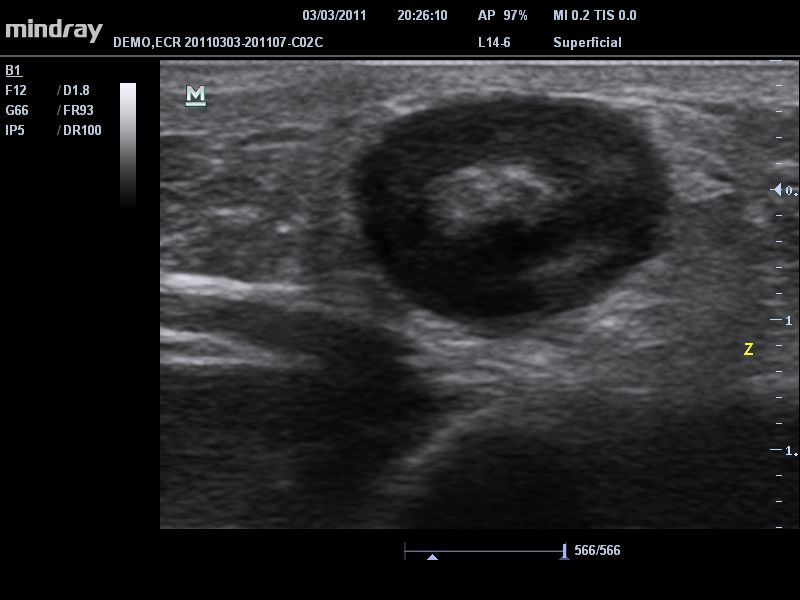

• B-Steer™ / iNeedle™: Функция маневрирования ультразвукового луча, улучшающая видимость иглы, нервных волокон и мелких сосудов.

• iBeam™: позволяет более точно определять границы благодаря объединению нескольких изображений, полученных под разными углами, в одно изображение в режиме реального времени.

• Линейный ультразвуковой датчик Mindray 7L4A

• Высокочастотный линейный датчик 38 мм Mindray l14-6NE